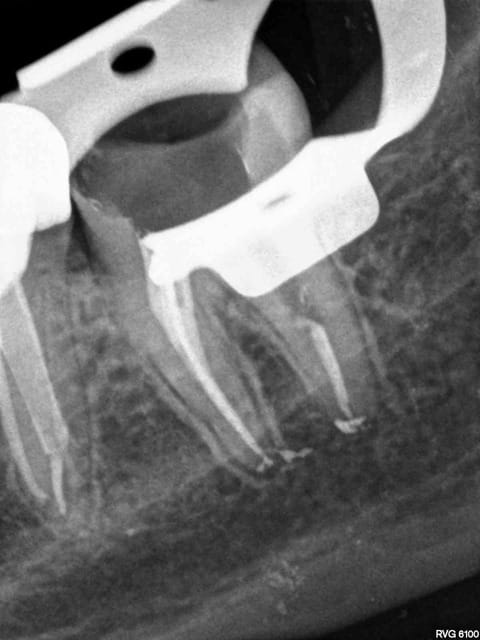

J'y travaille pour trouver un moyen simple et efficace pour poser la digue dans toutes les situations comme celle ci dessous. Tiens c'est tout frais, endo sc33 en 1 temps, 1H 15 et encore je n'ai pas d'assistante au fauteuil.

Pulpite indication endo. perte de substance: Indication onlay , mais pas dans le panier de soins donc sc 33, couronne coulée : patiente CMU.